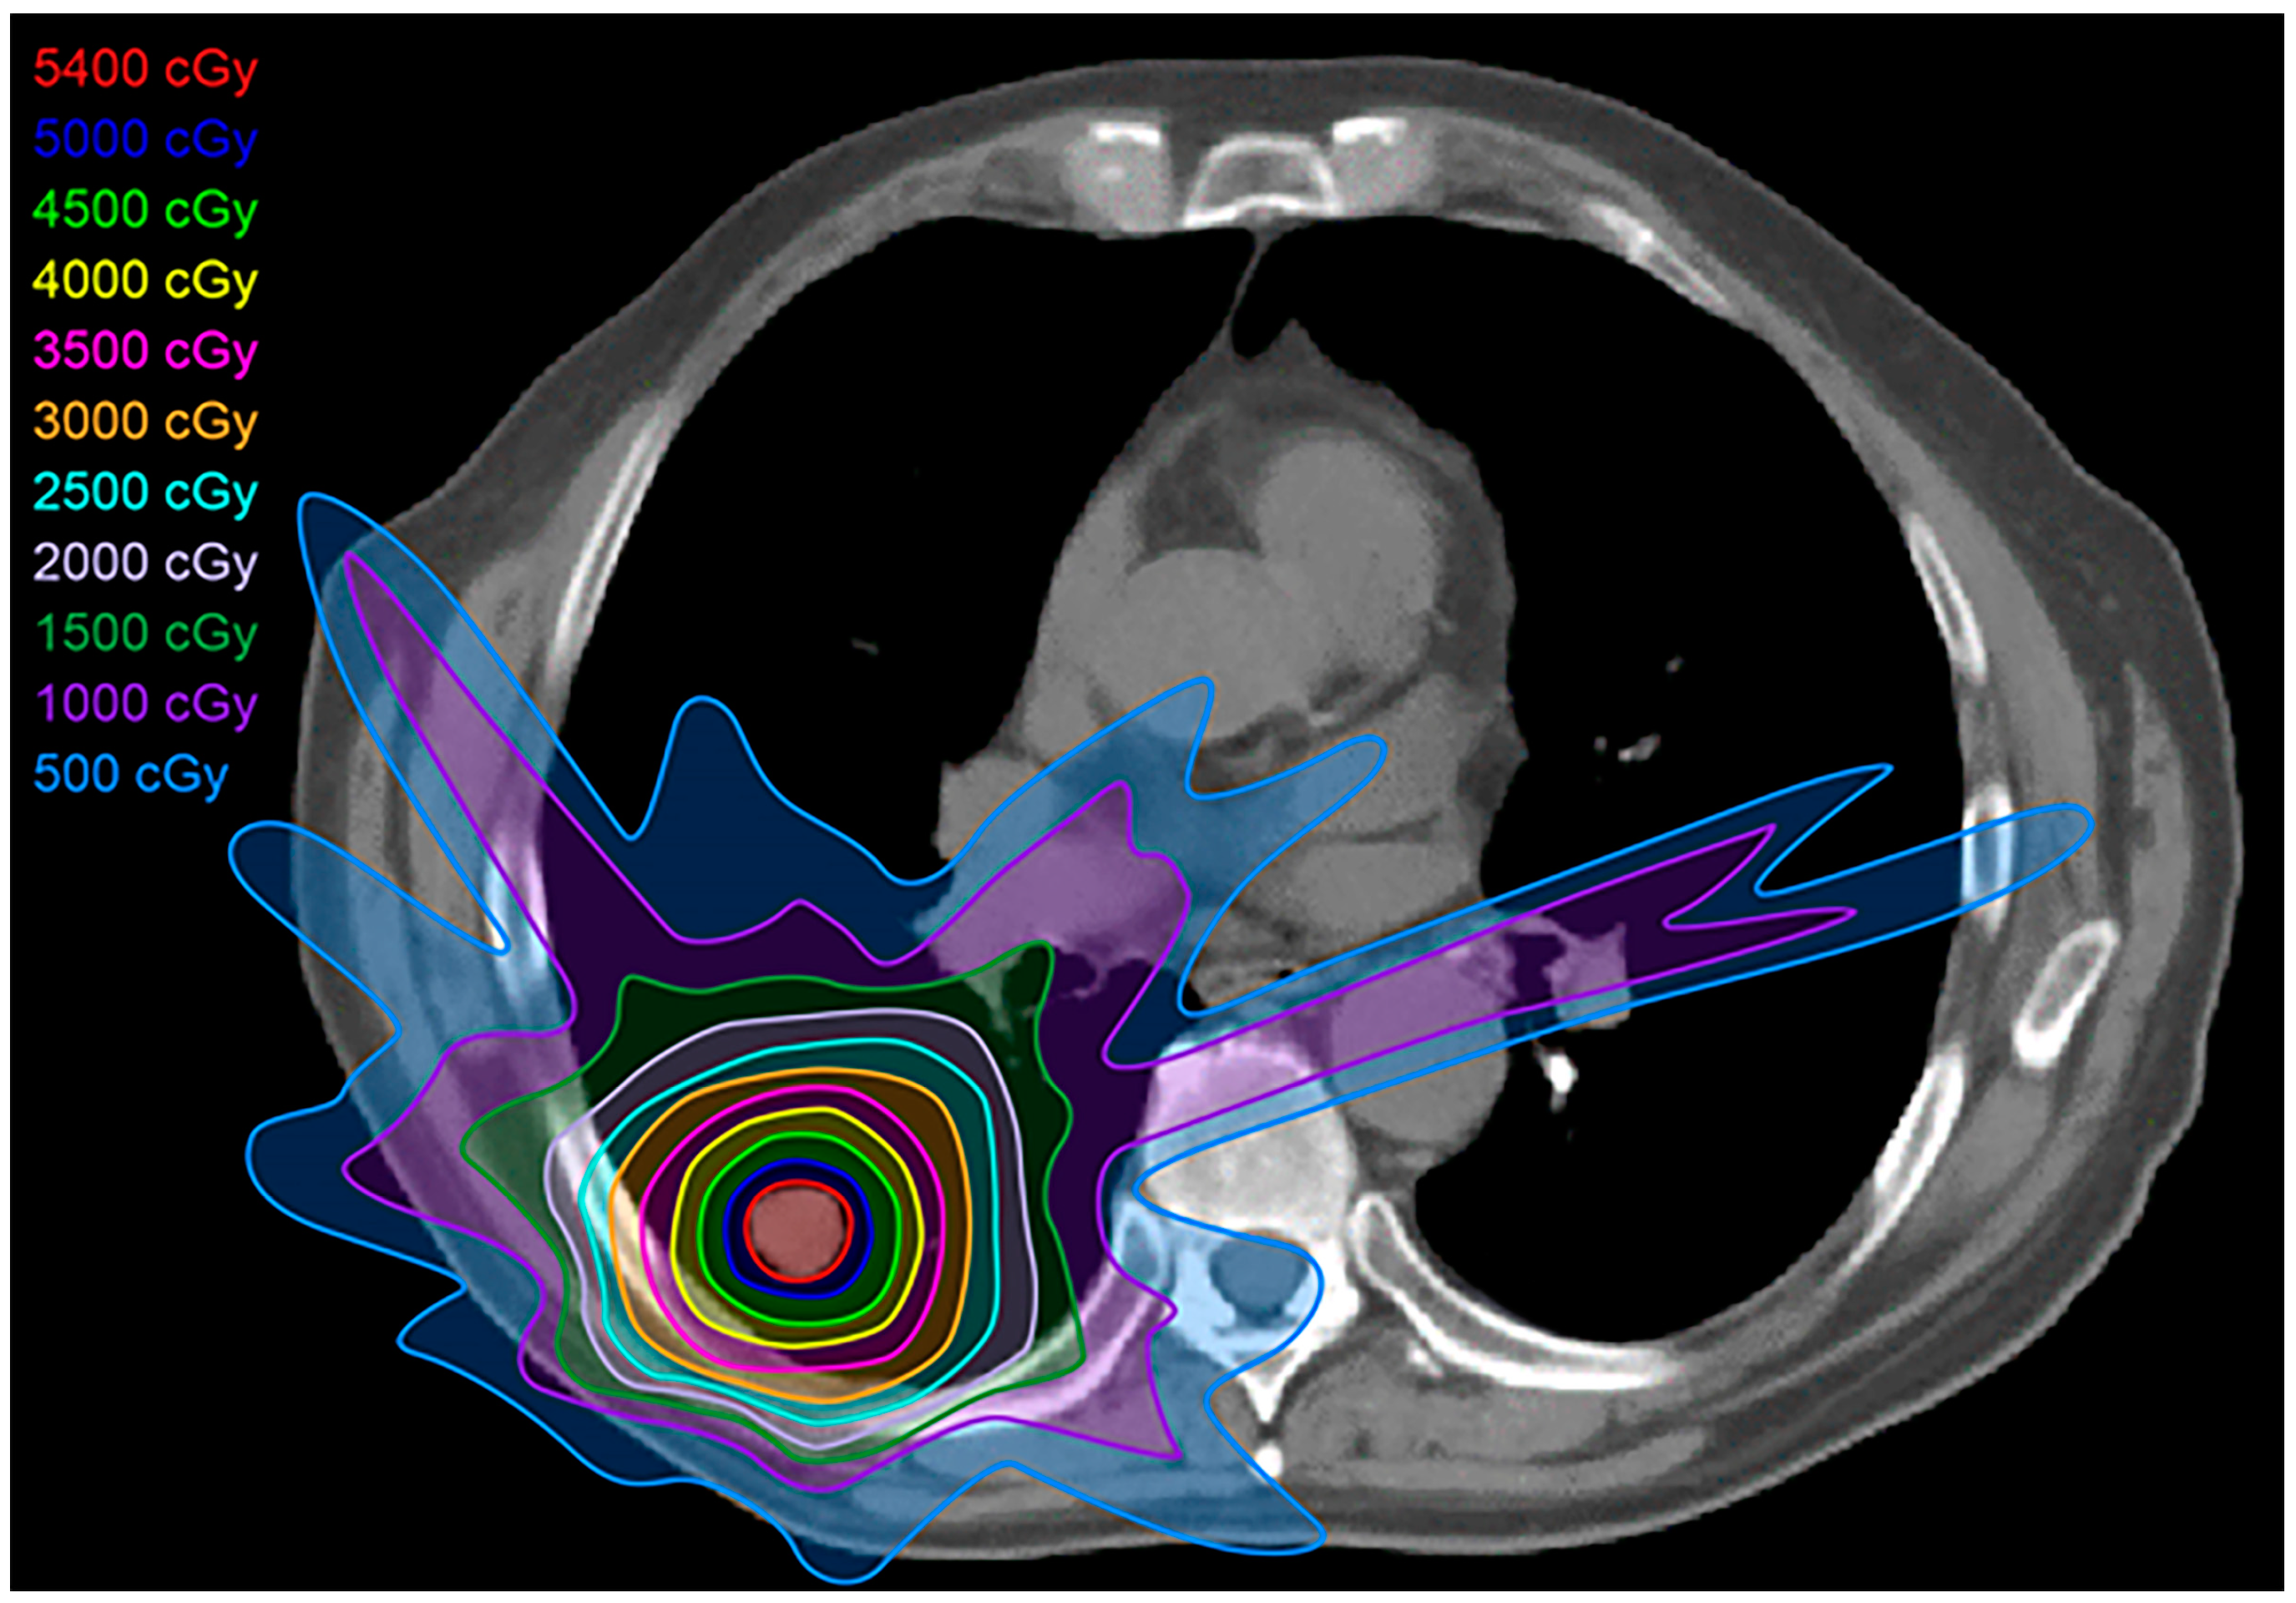

2.2. Three-Dimensional Conformal Radiotherapy

2.3. Intensity-Modulated Radiotherapy